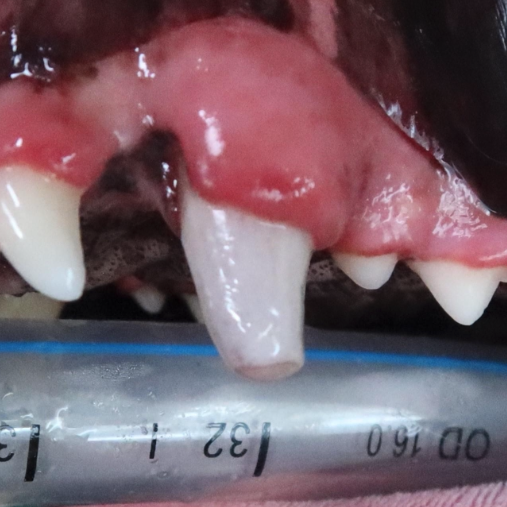

Example of a fractured canine tooth in a dog:

Before: